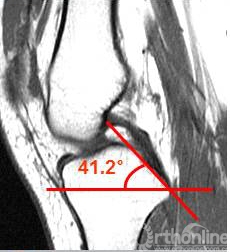

PCL的解剖特点及器械设计思路

●根据PCL解剖特点和数据设计器械

●长方形开槽更利于抗旋及固定